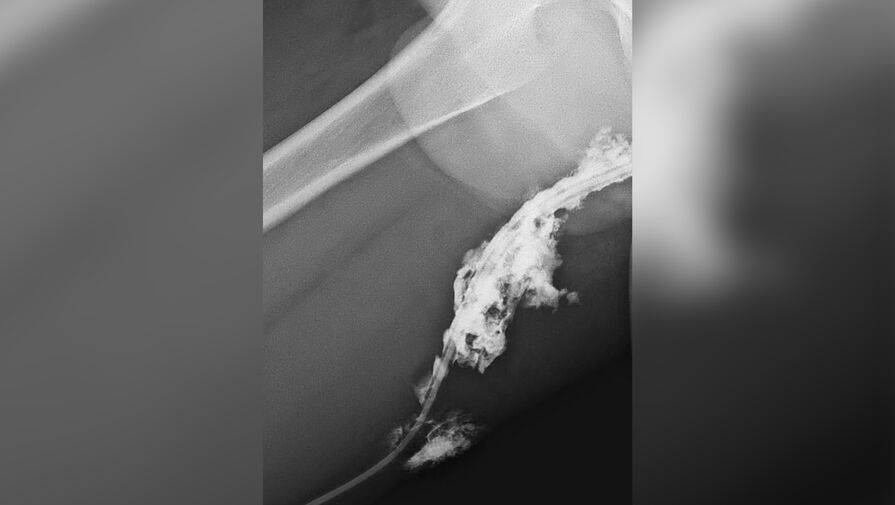

Подросток прыгнул с гаража и приземлился бедром на острый прут металлического забора. В больнице пострадавшему провели рентген с контрастом для выявления инородных тел в мягких тканях.

«Прут вошел достаточно глубоко, вплоть до седалищного нерва. Тем не менее, к счастью, жизненно важные структуры организма не были повреждены», — рассказал врач-травматолог-ортопед больницы Александр Нестеренко.